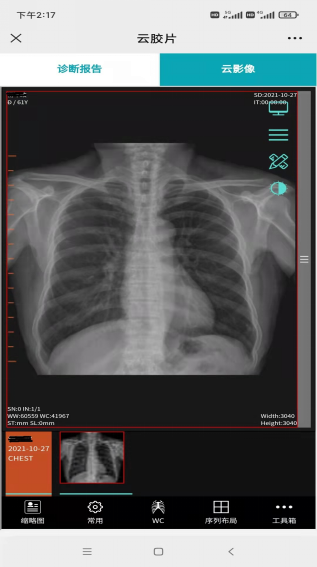

医学影像远程会诊实现服务新提升。2021年7月初组建区域 “云”影像诊断中心,依托健康数据云平台优势,构建阎良区域医学影像大数据云平台。平台以阎良区人民医院为中心,联通6个街道卫生院,为基层卫生院提供线上诊断,群众无需奔波就可享受二级医院的诊断水平,节约了医疗资源、降低了医疗费用。

“云”胶片替代传统影像胶片

手机查看拍片影像

远程诊疗高效协同。5G技术为疾病诊断、监护和治疗等提供的信息化、移动化和远程化医疗服务,实现了远程会诊、远程影像、远程心电、双向转诊等业务高效协同服务,既促进了优质医疗资源共享下沉,又提升了医院运营效率和诊疗水平。今年以来,区域“云”影像诊断中心累计诊疗报告数超7500例,远程心电数累计达11.9万次,群众就医体验持续改善。